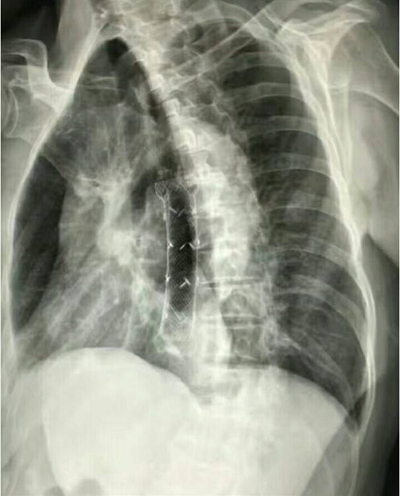

食道支架置入术后,食道管腔通畅

消化道造影梗阻好转

目前为止,我院共为200余名食道良恶性狭窄患者成功置入食道支架,食道支架治疗中晚期食道癌已成为临床治疗食道癌的重要手段,适用于不能耐受手术、手术风险高的高危患者,可有效改善晚期食道癌患者的生存质量,延长患者生存期。食道支架置入术为微创治疗技术,手术时间短,术后患者立即可进食,受到患者及家属的一致好评。